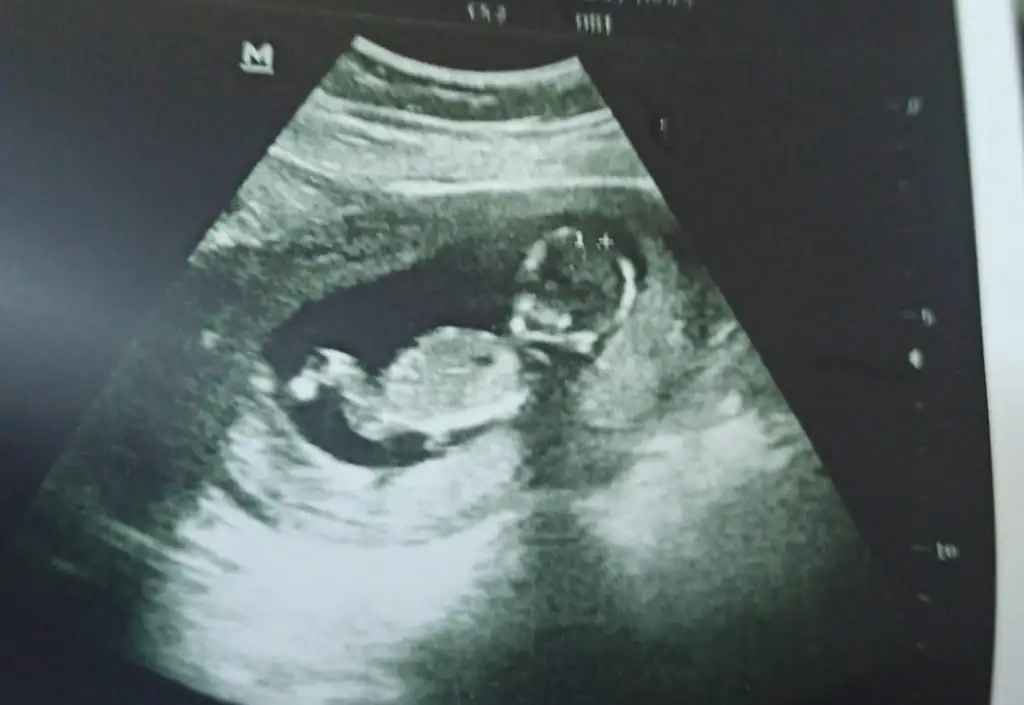

Erkek görünüyor

Emin olamadım erkek gibi sanki

Erkek gibi sanki emin olamadımMerhaba 12+2 di burda bende tahmin alabilirmiyim rica etsem

Şimdilik kız yönünde ama en iyi 11 12 13 haftalar olmalı